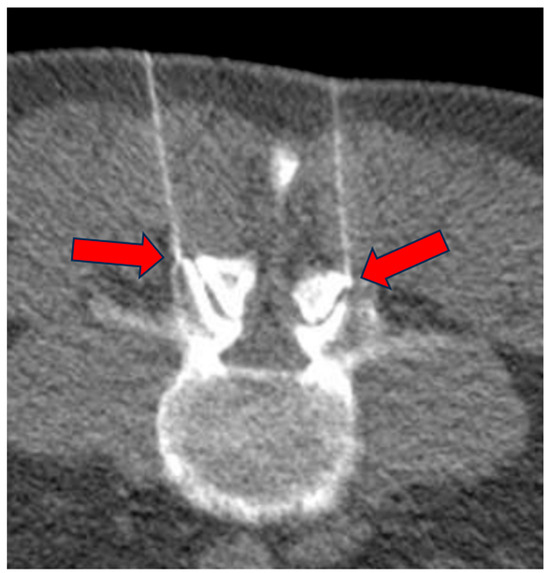

Typically, a 9 cm 22 G needle was used, but in some cases longer needles (up to 15 cm) were used depending on the patient’s anatomy. Another CT scan was then performed to confirm accurate needle placement (Figure 4).

Figure 4.

Low-dose CT scan for correct positioning of the needles at the facet joint level (arrows).